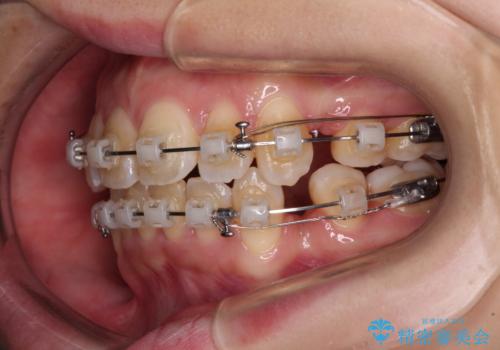

- クリアブラケット

口元を積極的に引っ込めるために、上下左右の小臼歯4本を抜歯し、目立たないワイヤー装置にて矯正治療を行うこととしました。

上下前歯の歯軸の角度が大きく改善され、お口を閉じたときに顎先に認められた梅干し様の皺も改善されました。